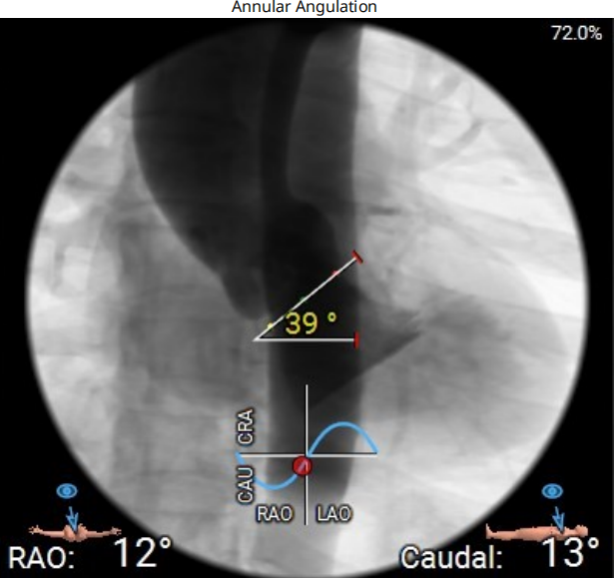

主动脉成角39°;